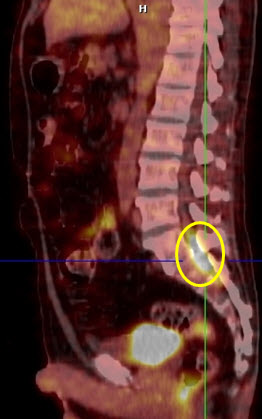

Hình 3. Bệnh nhân Lê V.T., nam, 73 tuổi. Chẩn đoán: U lympho ác tính không Hodgkin biểu hiện ở màng cứng ống tủy sống. Hình PET/CT cho thấy tổn thương tăng hấp thu FDG tại ống tuỷ sống (hình ovan).